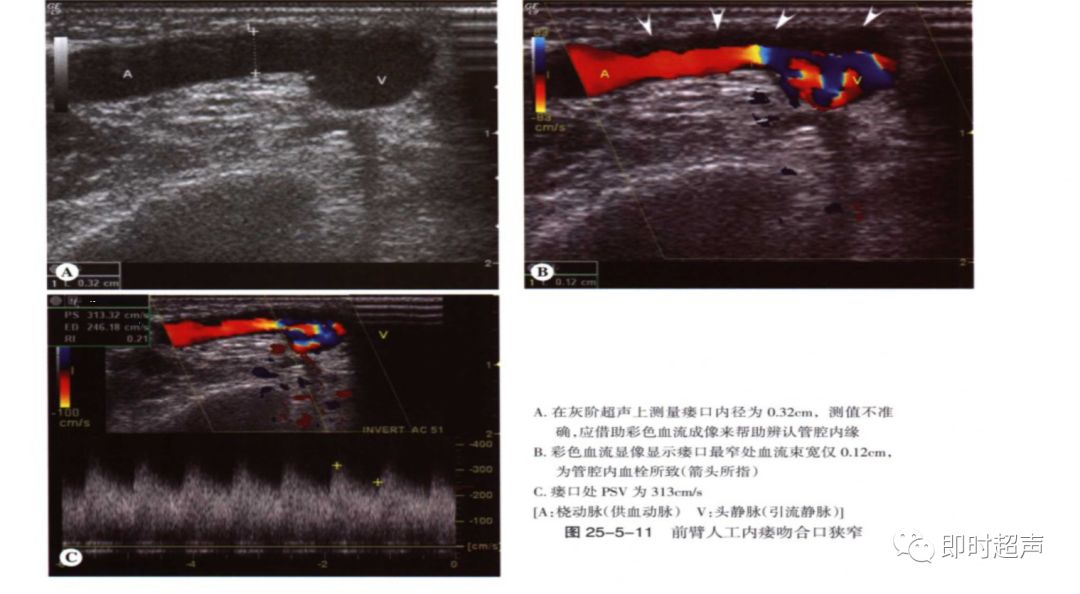

(2)吻合口狭窄:分别测量吻合口处PSV及其上游2cm处动脉PSV,计算比值, ≥3.0时考虑吻合口狭窄。

吻合口内径正常约3-5mm,若小于2.5mm,血流异常考虑吻合口狭窄。